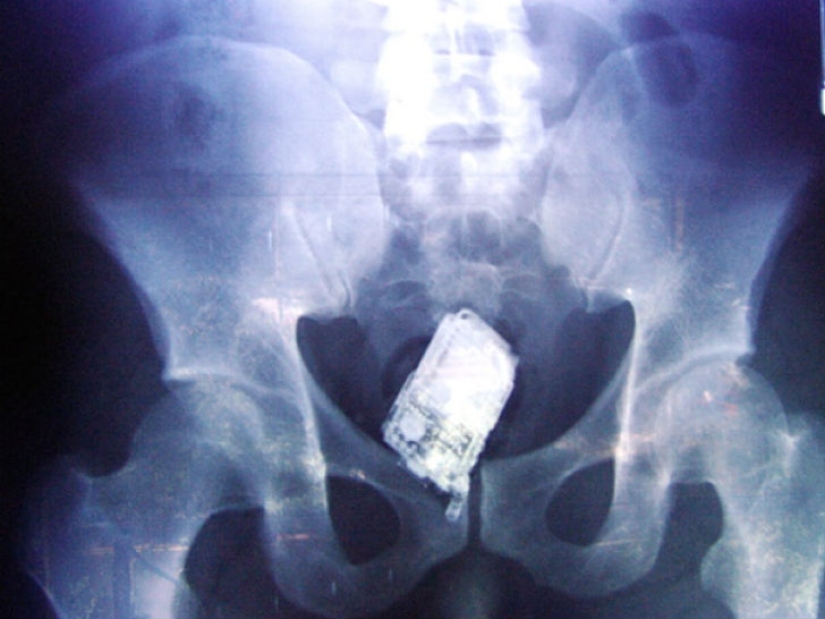

Y los prisioneros también tragan teléfonos celulares.